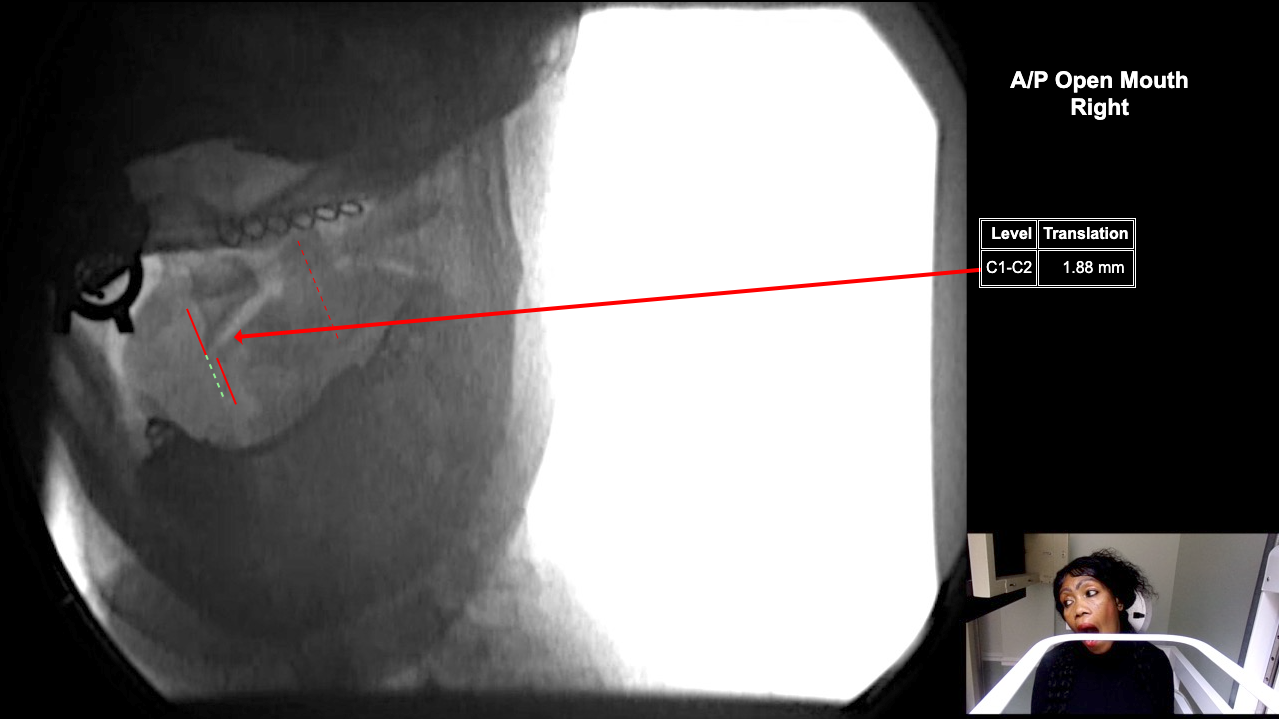

Home > Catherine Basseck 10-23-25